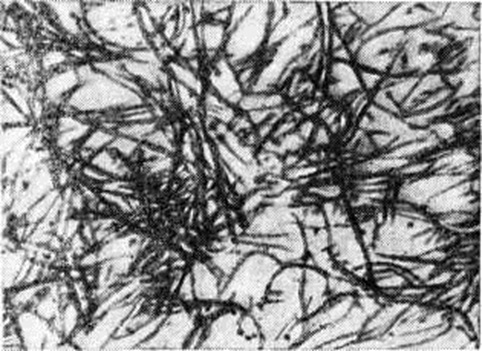

Рисунок 1.

Электронограмма гиалинизированной соединительной ткани: гиалин (фибриллярный белок) представлен в виде фибриллярных нитей; × 30 000.

Гиалиноз относится к внеклеточным (мезенхимальным) диспротеинозам. Появление в цитоплазме гиалиновых капель (гиалиново-капельная дистрофия) или шаров (гиалиновые шары) не связано с Гиалиноз. Гиалин является фибриллярным белком (рисунок 1), в построении которого принимают участие плазменные белки, в частности фибрин. При иммуно-гистохимические исследовании в гиалине обнаруживают не только фибрин, но и компоненты иммунных комплексов (иммунные глобулины, фракции комплемента). Гиалиновые массы стойки к действию кислот, щелочей, ферментов, хорошо окрашиваются кислыми красками (эозин, кислый фуксин), пикрофуксином красятся в жёлтый или красный цвет; в массах гиалина могут откладываться липиды, соли кальция. Внешний вид органов и тканей при Гиалиноз зависит от стадии процесса; чаще Гиалиноз ничем не проявляется и обнаруживается лишь при микроскопическом исследовании. В тех случаях, когда процесс выражен резко, ткани становятся бледными, плотными, полупрозрачными. Гиалиноз, в частности артериол, может привести к деформации и сморщиванию органов (например, развитие артериолосклеротического нефроцирроза, клапанного порока сердца).